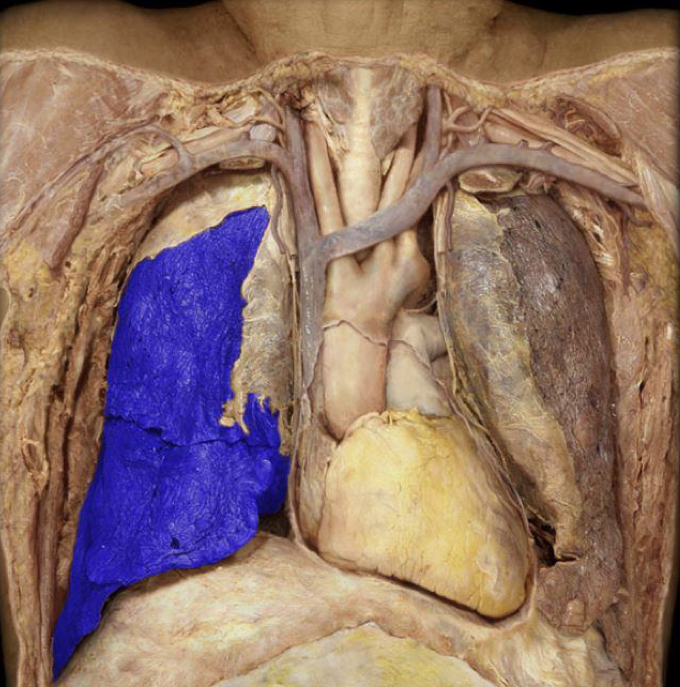

What structure is highlighted in blue?

Left lung